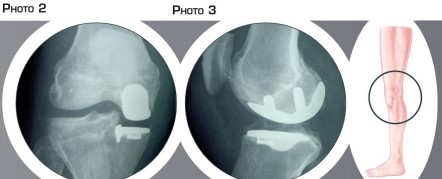

Un passage est fait sur le côté de la rotule pour accéder à l’articulation, Le cartilage usé est enlevé. Le cartilage sain est préservé ainsi que l’ensemble des ligaments. La partie usée du fémur et la partie usée du tibia sont préparées (figure T n°3). La prothèse comportant une pièce fémorale et une pièce tibiale est alors implantée de manière à assurer une stabilité parfaite du genou et une mobilité la plus complète possible [figure n°4, photo n°2 et n°3).